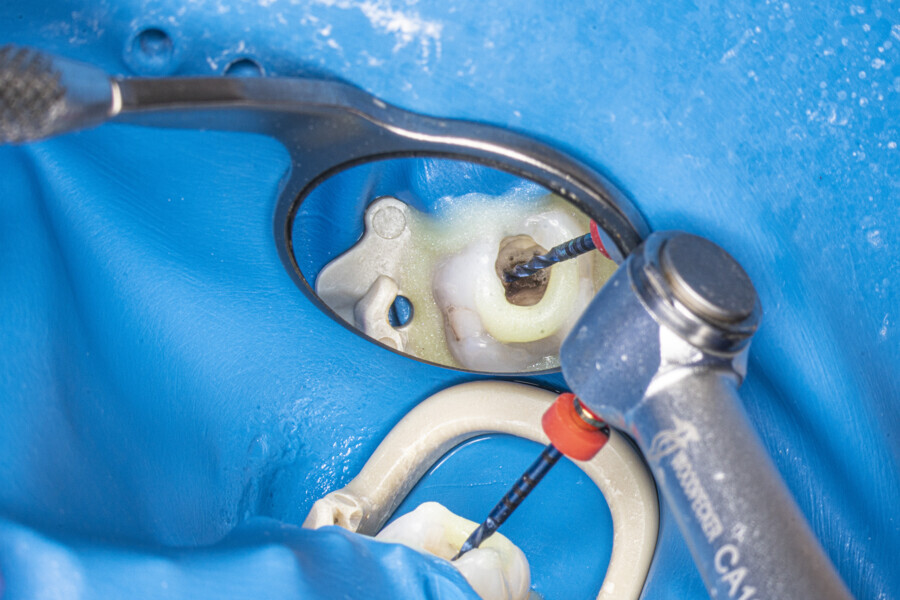

The first trials of the LPE concept were performed on extracted human molars. Although the dynamics of fluid during root canal irrigation are completely different in vivo than in extracted teeth, these kinds of trials provide initial information about the procedure. Some of these teeth had apices closed with a coat of wax and composite resin to close the apical delta and simulate the periapical tissue. After creation of the access cavity, the pulp chamber was cleaned with continuous irrigation with 5.25% NaClO activated with a SkyPulse laser (Fotona) in AutoSWEEPS mode (20 Hz, 15 mJ). A 25/0.07 reciprocating file (Shenzhen Perfect Medical Instruments) was used to perform the pre-flaring procedure. After opening the coronal third, continuous irrigation with 5.25% NaClO activated with the laser was used to clear the debris for 30 seconds. After removing the debris, a #10 C-PILOT file (VDW) was used to establish apical patency, without forcing the file if possible. In some cases, apical patency was reached already at this stage of root canal preparation. In all cases, the second step of instrumentation was the preparation of the middle third with the same file, and the same irrigation procedure was performed. Subsequently, the C-PILOT file was used to reach the apical foramen. At this stage, apical patency was reached in most cases, but in some roots, there was no possibility of entering the apical foramen. The working length was confirmed with a radiograph with the hand file. Usually, the next procedure to be done is apical preparation, but the LPE concept is based on an enhanced irrigation protocol. Following this protocol, irrigation was performed for 5 minutes with continuous flow of 5.25% NaClO activated with the SkyPulse laser in AutoSWEEPS mode (20 Hz, 20 mJ) with a conical sapphire fibre. The next step was alternating irrigation with 17% EDTA for 30 seconds, with 5.25% NaClO for 30 seconds and with 17% EDTA for 30 seconds, all activated with AutoSWEEPS, followed by irrigation for another 5 minutes with 5.25% NaClO activated with AutoSWEEPS. In most cases, the next step after this stage of enhanced irrigation was the calibration of the apical constriction rather than apical preparation per se, but this step requires further investigation.

1. Pre-flaring up to size 25/0.06 or 30/0.08 (or with your favourite orifice opener)

2. Irrigation with NaClO with SWEEPS activation for 10–15 seconds

3. Instrumentation to two-thirds of estimated working length up to size 25/0.06, 25/0.07 or 25/08

4. Establishing patency with a #10 hand file (if possible at this stage)

5. LPE enhanced irrigation protocol

6. Establishing patency with a #10 hand file

7. Apical preparation (an apical gauging procedure can be useful)

8. Final irrigation protocol